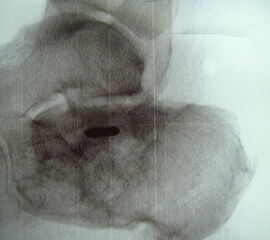

Abbildung Nr. 14-16

Reseziertes Os trigonum sowie prä- und postoperatives seitliches Röntgenbild nach arthroskopischer Entfernung eines Os trigonum.

Abbildung Nr. 19-22

Knochenresektat sowie präoperatives CT (Sagittal- und Transversalebene) und intraoperative Bildwandlerkontrolle im seitlichen Strahlengang nach arthroskopischer Entfernung multipler Ossikel am dorsalen OSG/USG.